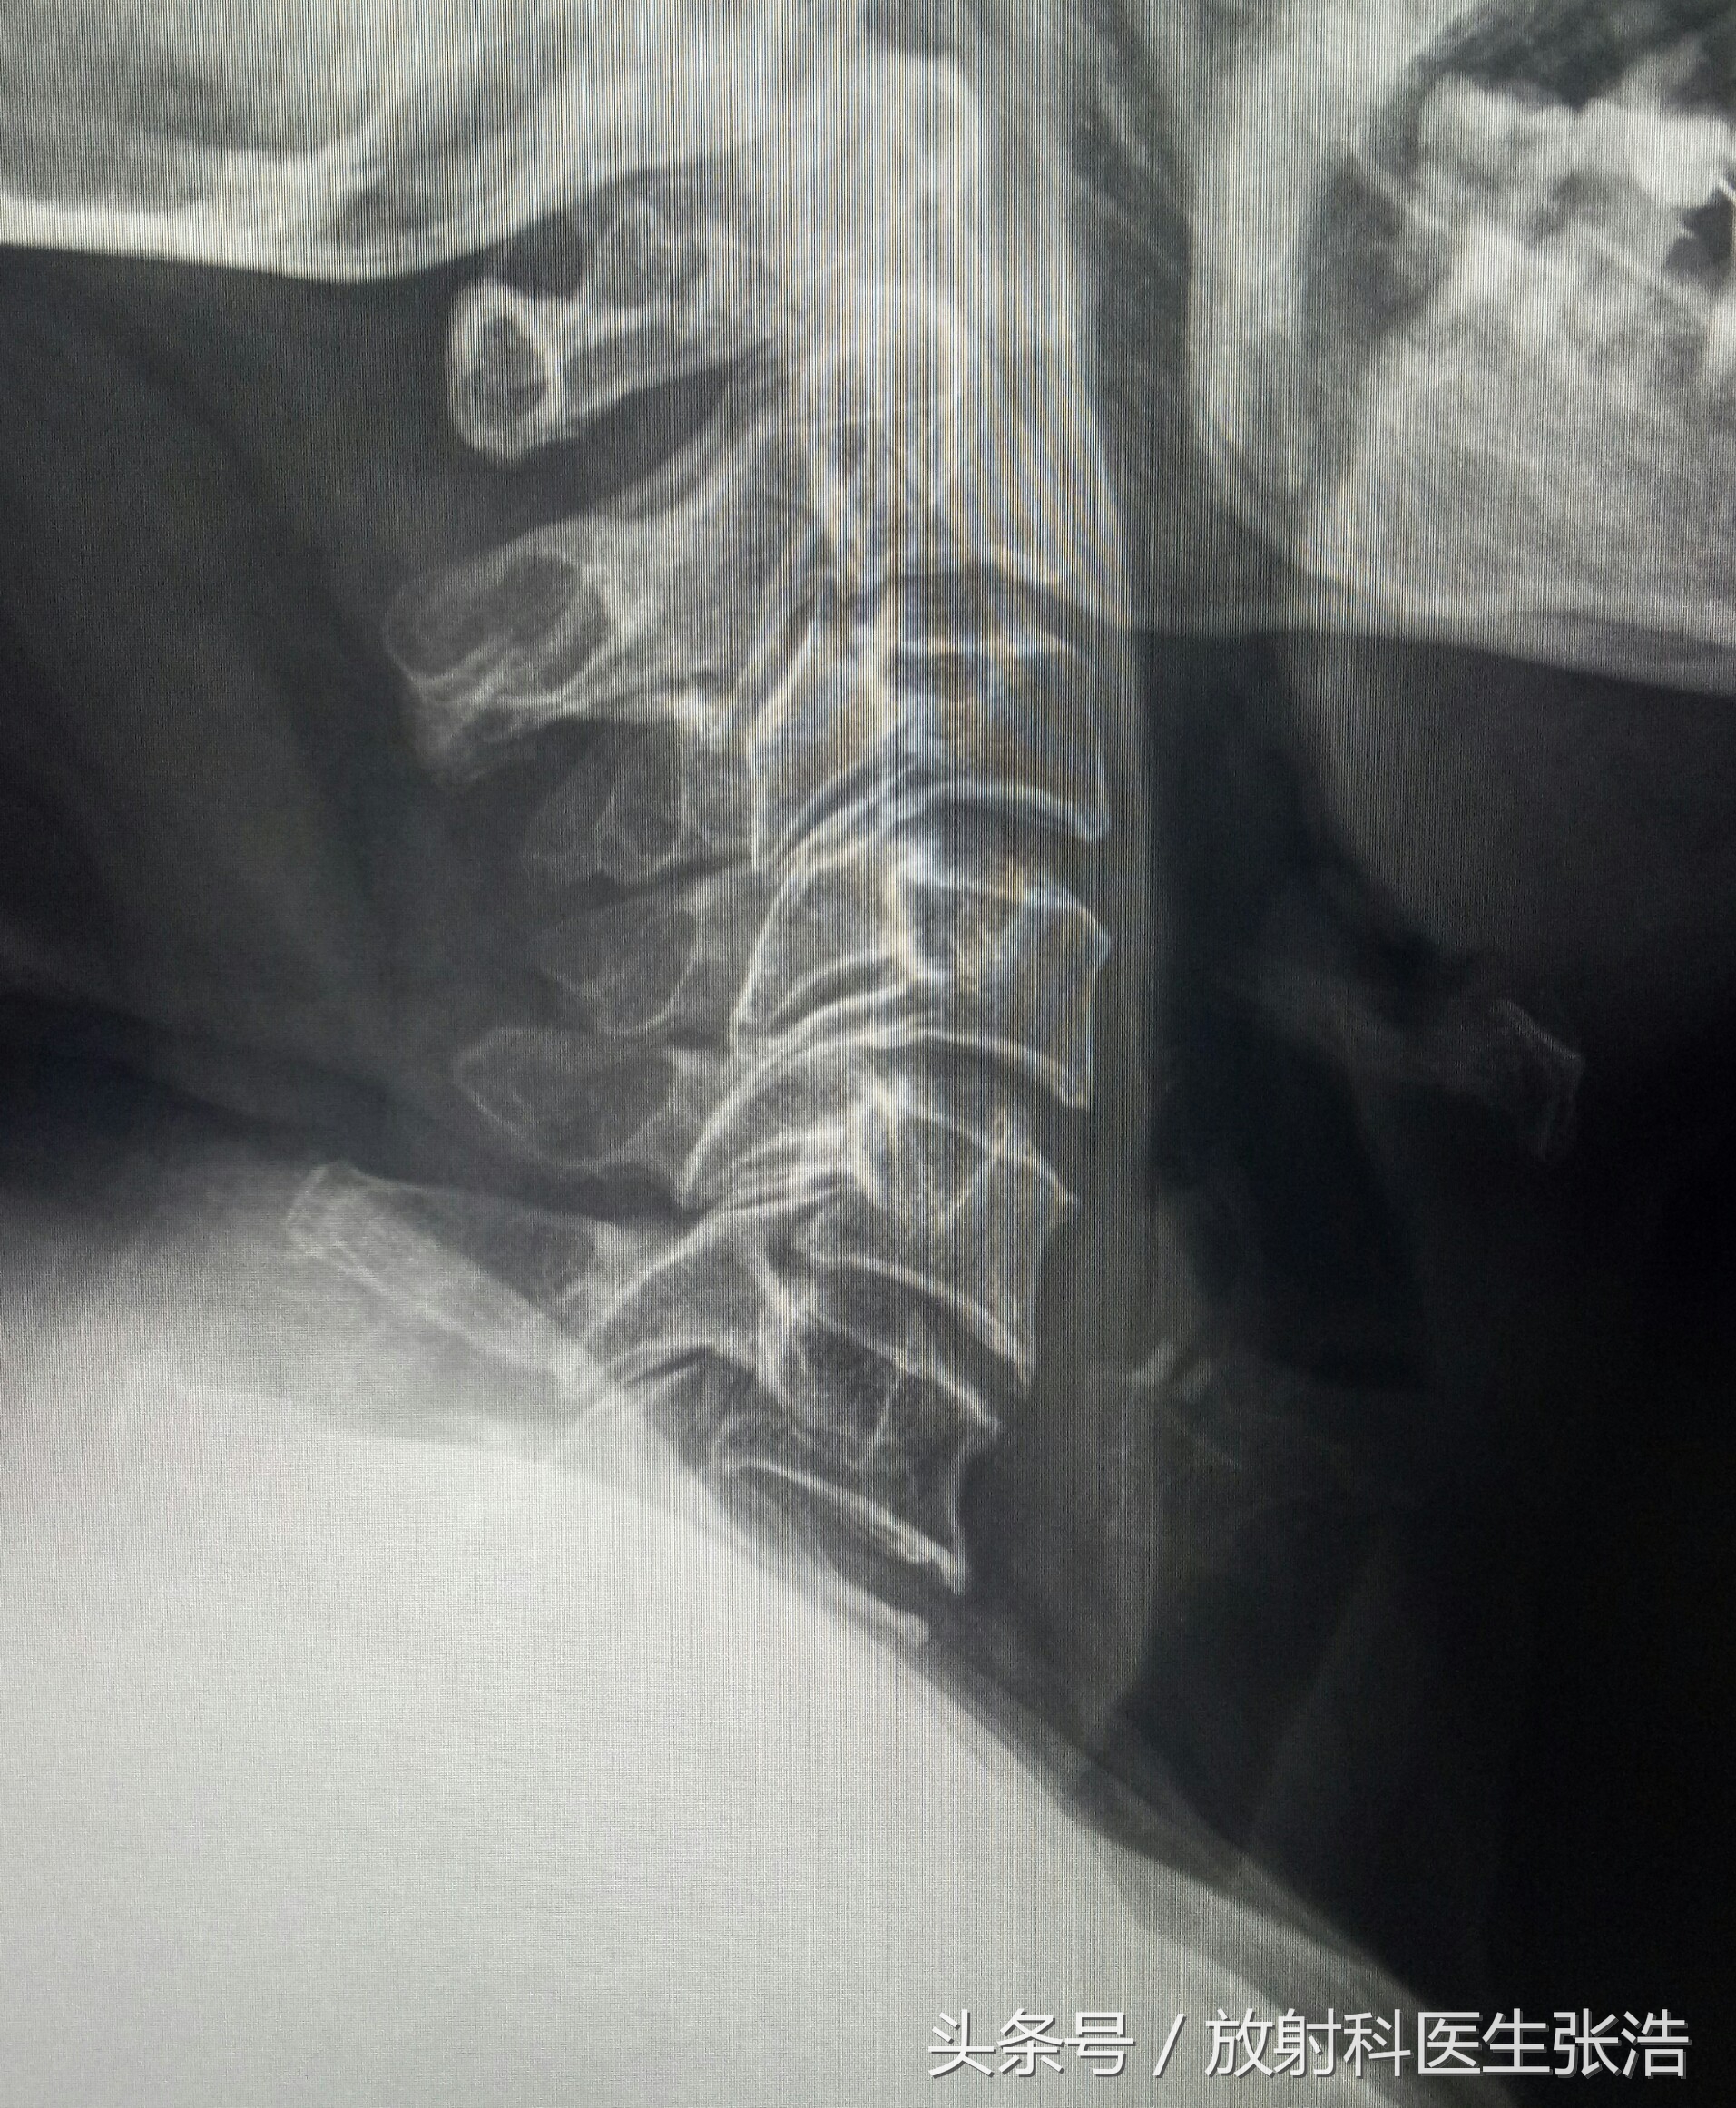

上面这是腰椎和颈椎增生的患者,可以看到椎体缘有明显的骨质增生,因为椎体前后有前纵韧带后后纵韧带,过多的增生往往会影响其活动度,有的增生会压迫到硬膜囊神经根等,所以会造成要背脖子僵硬不适。